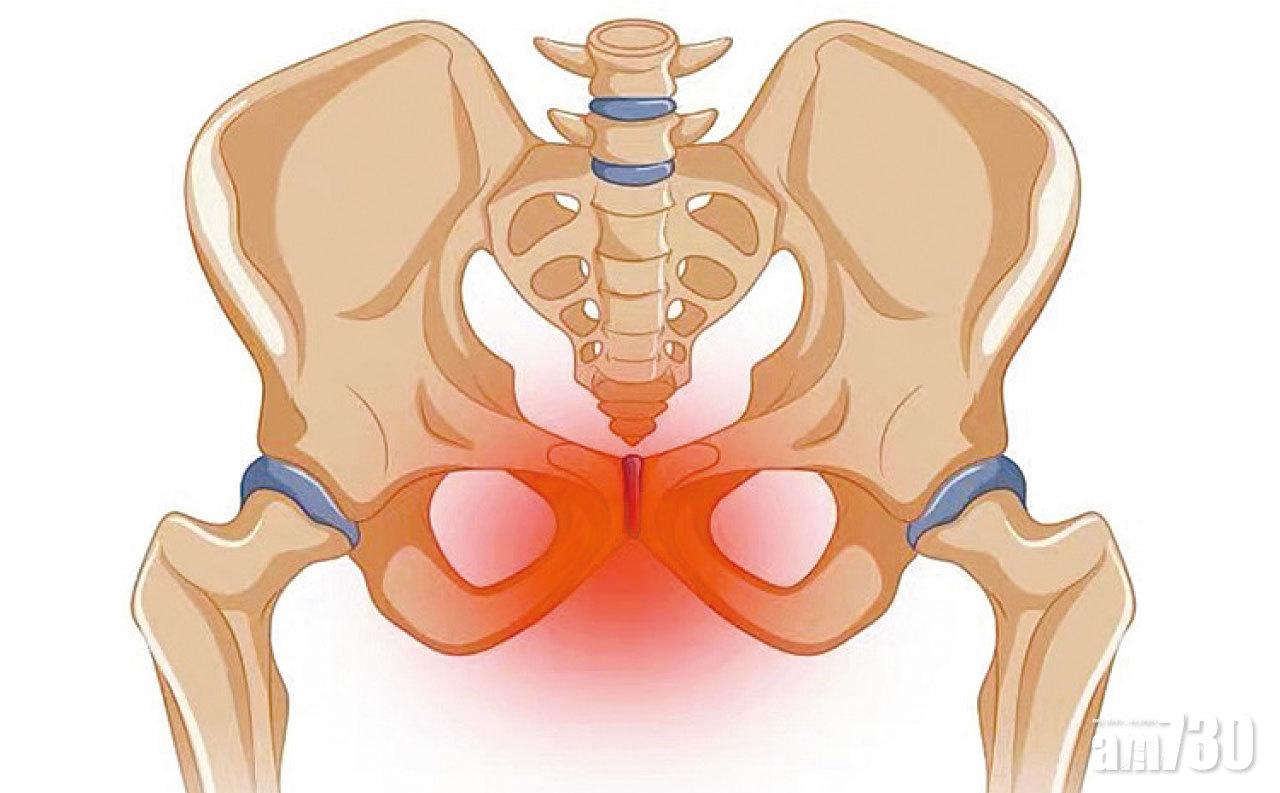

懷孕時受著荷爾蒙的影響,身體多方面會出現變化以配合胎兒生長和預備分娩的需要。其中鬆弛素和黃體素兩種激素有助鬆弛韌帶,使骨盆彈性增大,讓胎兒有更多的成長空間,也預備臨盆時能順利生產。但當恥骨韌帶過度鬆弛,做成恥骨聯合分離,韌帶受牽扯繃緊便會產生疼痛,甚至構成行動不便,痛勢難耐。